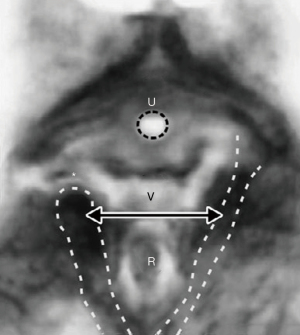

Con referencia a la Figura 10, en el punto "3" la cabeza (círculo) puede sobreestirar los ligamentos uterosacros (USL) para causar prolapso uterino y enterocele. Si las inserciones ligamentarias laterales del USL al recto "R" tiran de la pared anterior del recto hacia adelante a medida que los USLs se alargan, la pared anterior del recto puede estirarse hacia adelante y causar intususcepción rectal (11) (Figura 11), que puede curarse mediante la reparación de los USLs (12); En el círculo "2", el alargamiento o ruptura de los CL puede causar cistocele (defecto transversal); en el círculo "4", el daño perineal puede causar rectocele y síndrome perineal descendente; en el círculo "1", el exceso de presión sobre los músculos elevadores puede desplazar o desgarrar sus inserciones colágenas en el pubis, mientras que el exceso de presión sobre el PUL puede causar incontinencia de esfuerzo.